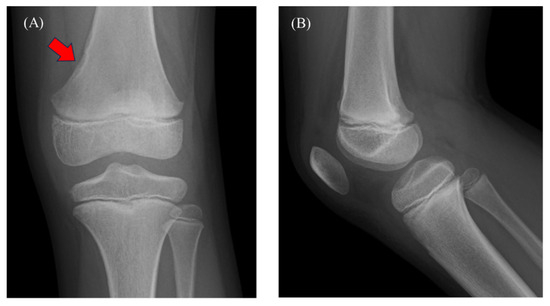

This report describes a rare case of a pediatric tenosynovial giant cell tumor (TSGCT) with a delayed diagnosis. A 9-year-old boy presented with a 3-month history of knee pain and swelling, initially attributed to a femoral non-ossifying fibroma and arthritis based on computed [...] Read more.

This report describes a rare case of a pediatric tenosynovial giant cell tumor (TSGCT) with a delayed diagnosis. A 9-year-old boy presented with a 3-month history of knee pain and swelling, initially attributed to a femoral non-ossifying fibroma and arthritis based on computed tomography findings and slightly elevated C-reactive protein levels. The symptoms persisted despite medical treatment. Magnetic resonance imaging (MRI) revealed a tumor in the posterior compartment. He underwent surgery, and the pathology confirmed the diagnosis of localized TSGCT. Six months postoperatively, the patient remained asymptomatic. Pediatric knee pain is a complex symptom associated with inflammatory conditions and benign and malignant tumors. Benign tumors, as in this case, can be misdiagnosed as arthritis, delaying diagnosis and treatment. MRI is recommended in cases involving symptom persistence. However, histopathological, immunohistochemical, and morphological examinations are crucial for definitive diagnosis, particularly when the imaging findings are inconclusive. Full article